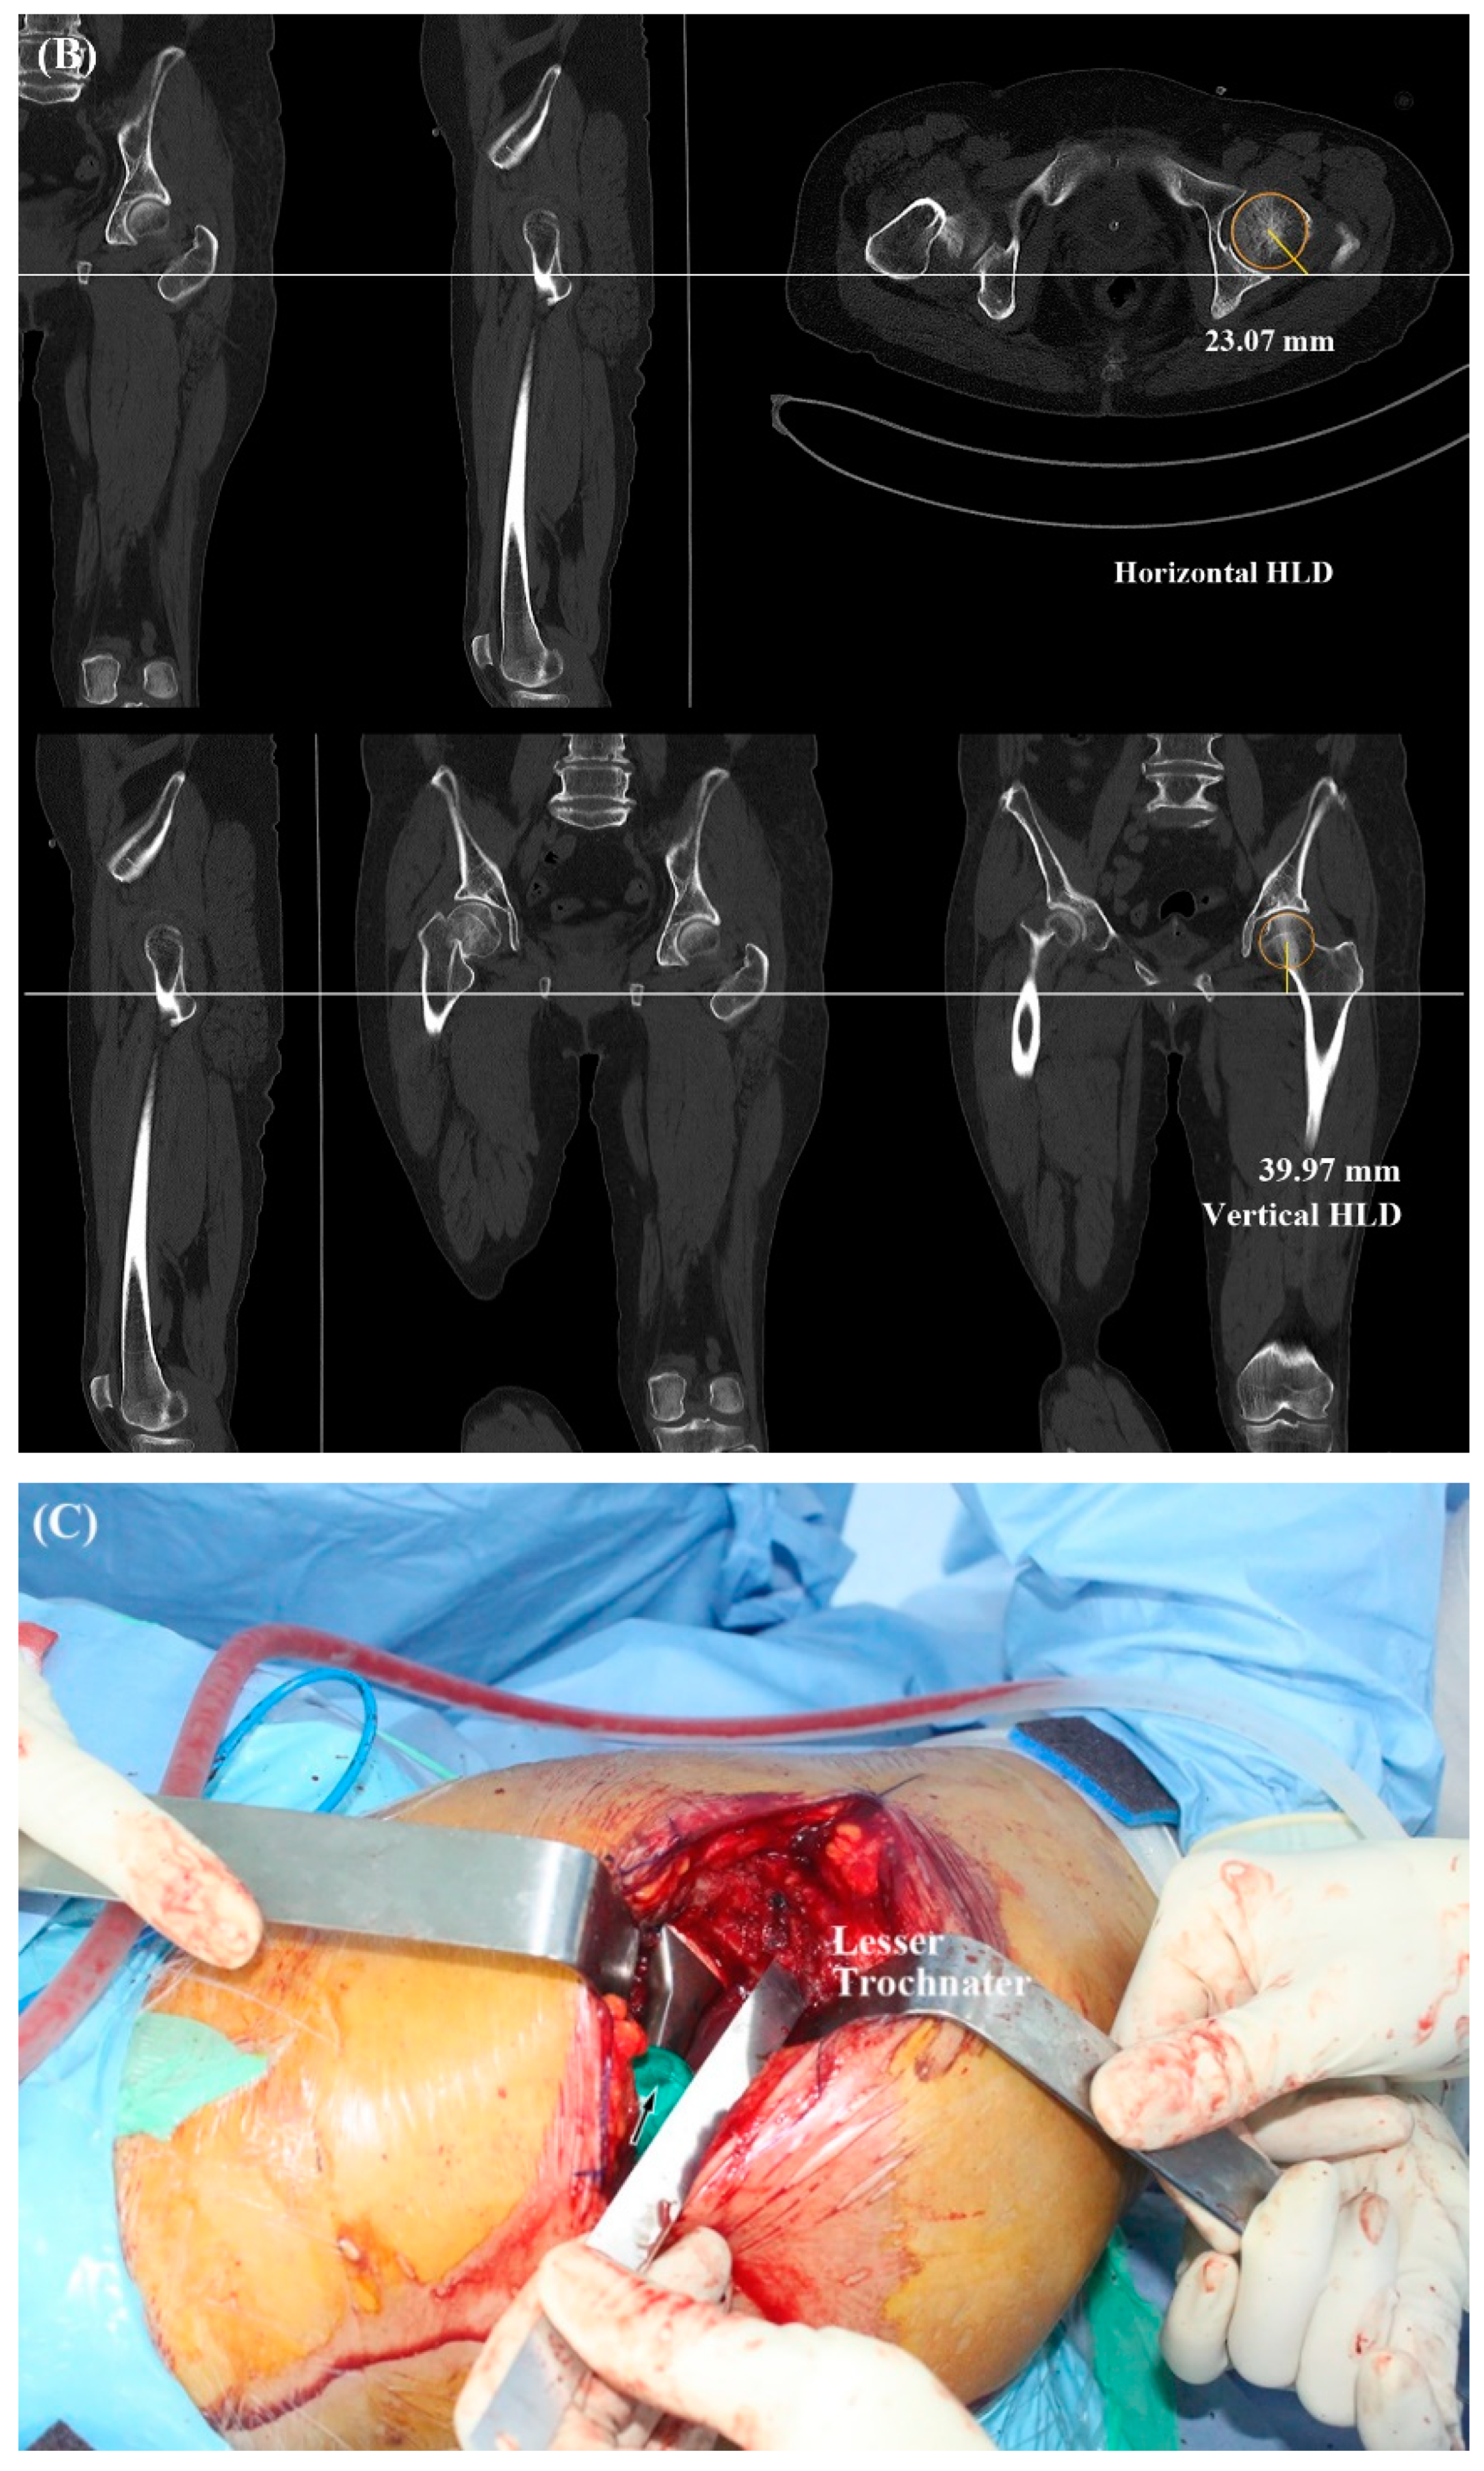

2.2. Radiologic Parameters

2.3. Operative Technique

| 3-D HLD | - | 45.9 ± 3.6 | N/A |